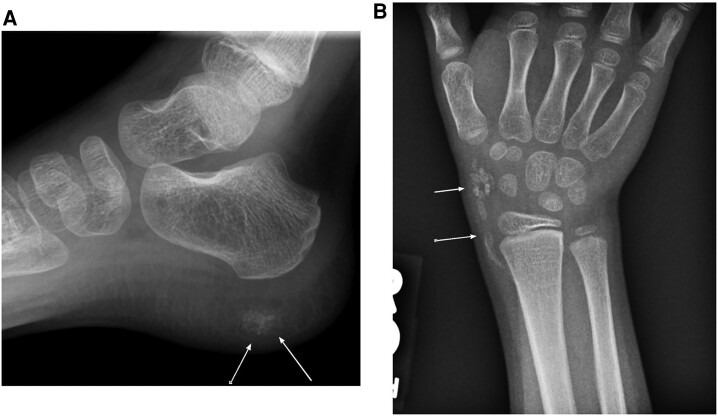

Progressive osseous heteroplasia (POH) is a rare autosomal-dominant hereditary bone disorder caused by inactivating pathogenic variants in GNAS1. POH is characterized by progressive cutaneous ossification and heterotopic ossification in skeletal muscles and subdermal connective tissues. Understanding of the natural history and phenotypic heterogeneity of the illness is incomplete. We report 2 affected male subjects with a milder than usual clinical course, highlight their clinical presentations and molecular correlates, and propose sodium 18F-fluorine positron emission tomography (PET) scanning as a sensitive technique for POH diagnosis and management.